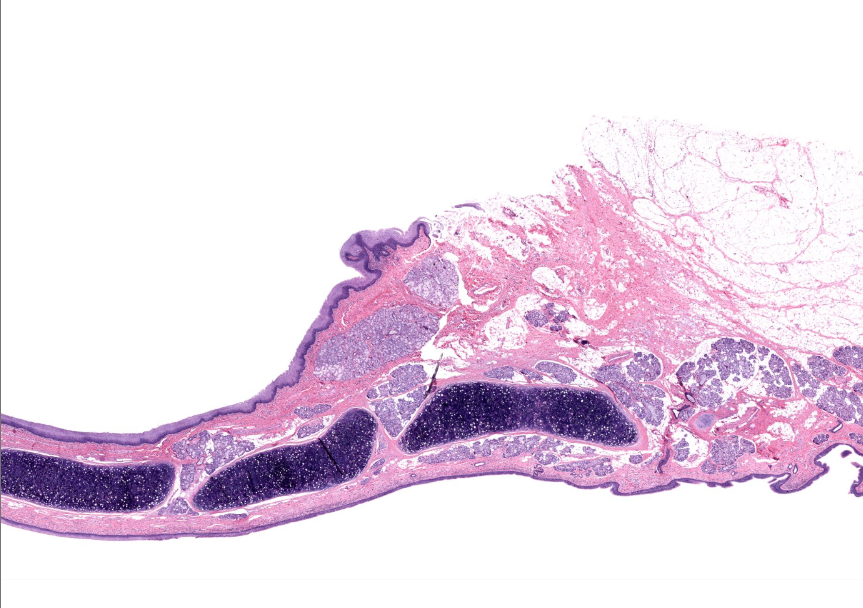

epiglottis

tissue type

strat. squamous non-keratinized epi

found on anterior/lingual surface of epiglottis

(tissue type)

respiratory epi

aka ciliated pseudostratified epithelium

found on posterior/trachea side of the epiglottis

lamina propria of the epiglottis

supports epithelium